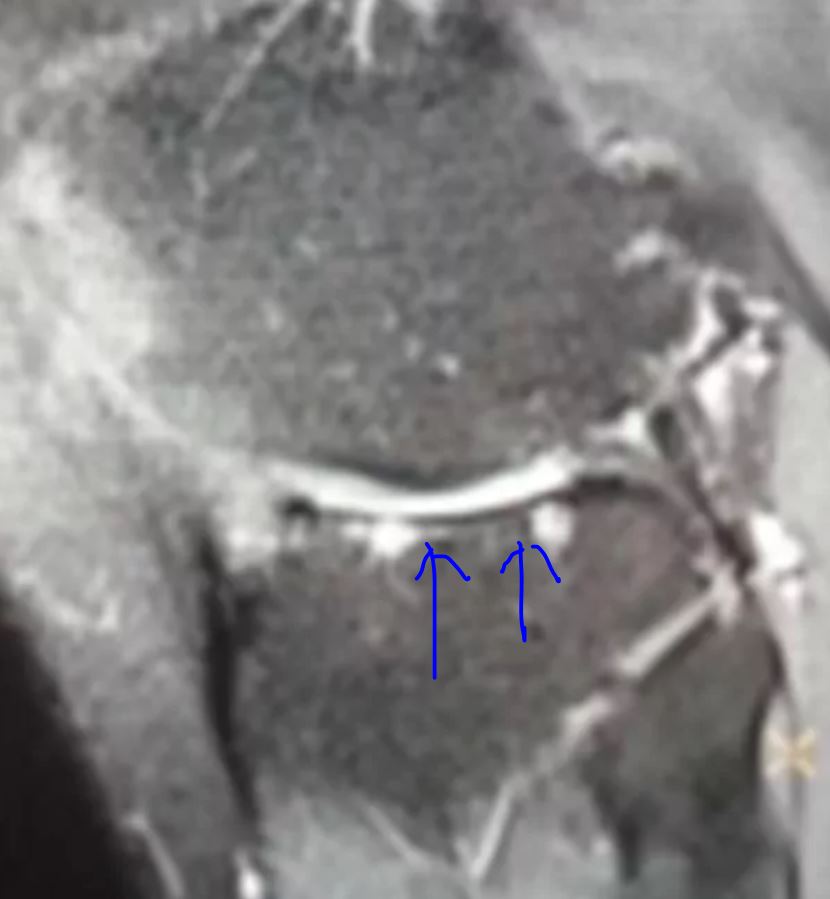

【3】核磁上半月板信号的分为0-3级

Grade 0: 正常

Grade 1: 内部球形高信号,未达关节面

Grade 2: 内部线形高信号,未达关节面,可达关节囊缘

Grade 3: 内部高信号达到上、下关节面或游离缘

半月板内出现3级高信号提示有撕裂,此3级信号必须确切,最好在连续两层上都能显示。在成人半月板内出现1或2级信号提示退变(粘液变性),如果是儿童或青少年出现1或2级信号则多为正常(血管尚未完全退化、半月板内的联络纤维)。